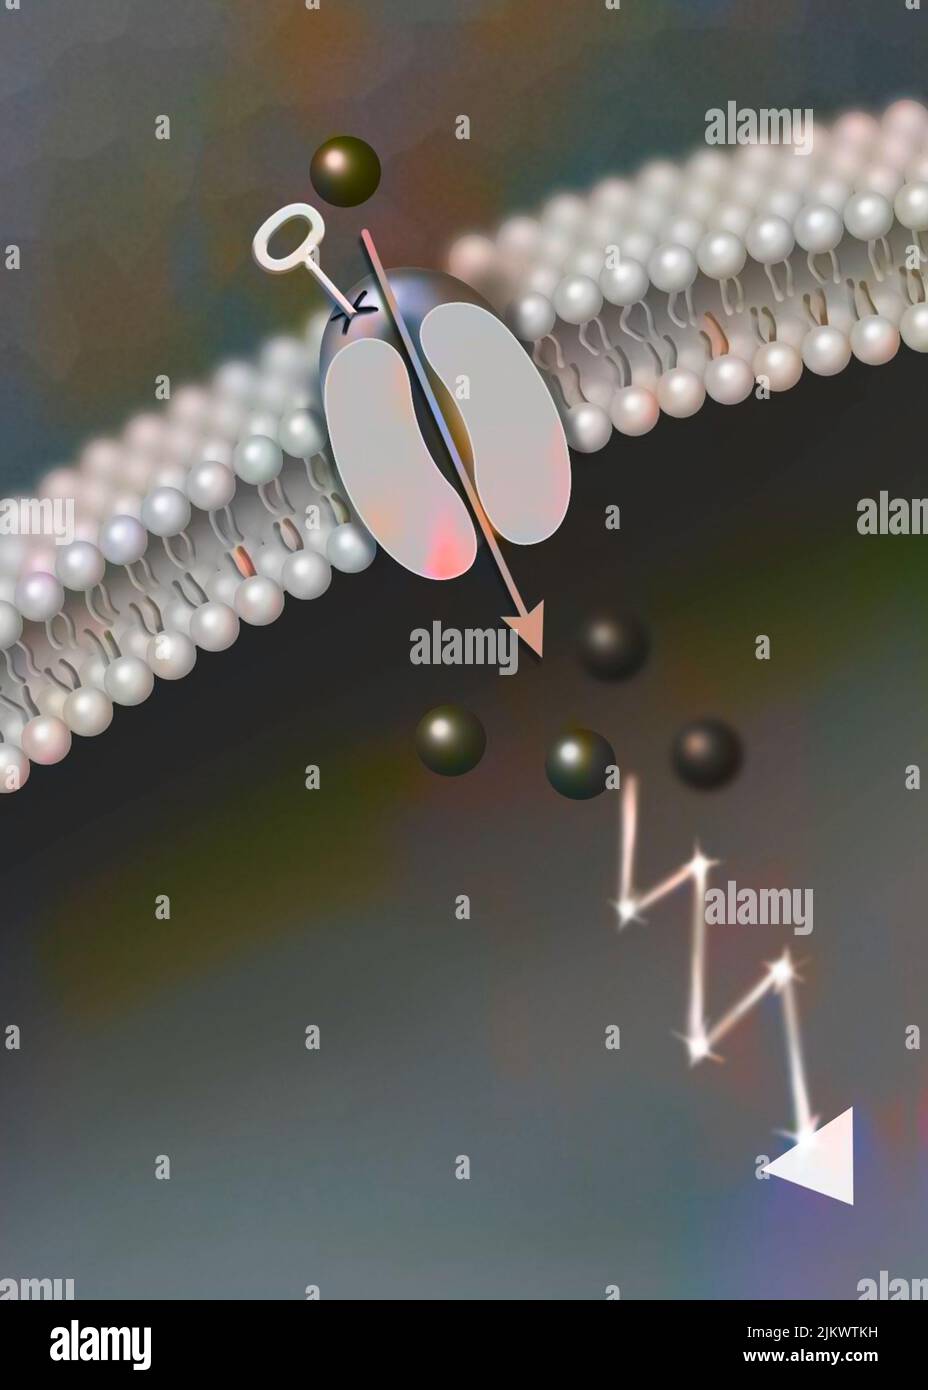

RF2JKWTKH–Canal ionique dépendant du ligand : l'attachement d'une molécule particulière provoque l'ouverture du canal.